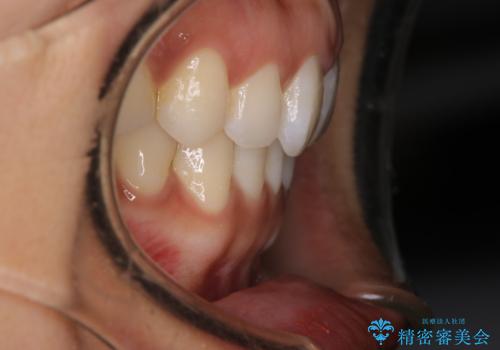

【インビザライン】前歯をきれいな歯並びにしたい

- 前歯の叢生を主訴に来院されました。このケースは抜歯をせずにIPRにてスペースを確保し、並べる計画をたてました。

きちんと使用時間を守って使用していただいたことで短い期間で治療が終了しました。